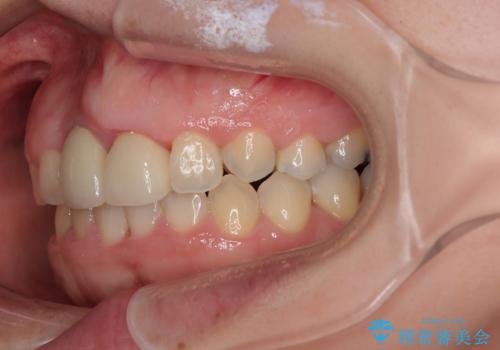

- 前歯のデコボコと、着色が著しい保険診療の前歯クラウンを気にして来院された患者様です。

前歯のクラウンは変色が顕著なため、矯正治療後にオールセラミッククラウンによる補綴治療を行うこととしました。

前歯のクラウンは、歯肉内深くに削り込まれており、歯肉の炎症が継続していたため、矯正治療後に歯周外科処置を行い、歯肉の腫れを改善させました。